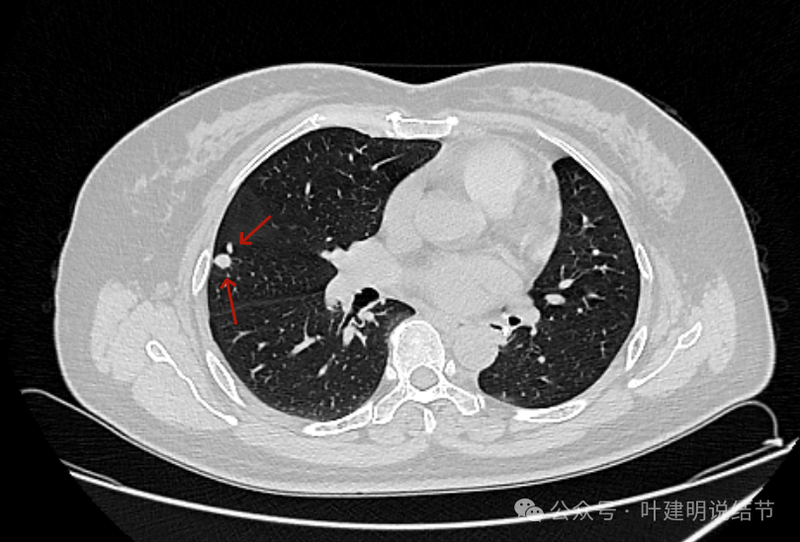

似乎两个中心点,密度均是实性的。

两个中心,病灶边缘光滑,轮廓清楚。

靠着水平理解 ,病灶缺乏收缩力。

叶裂于此处略有增厚。